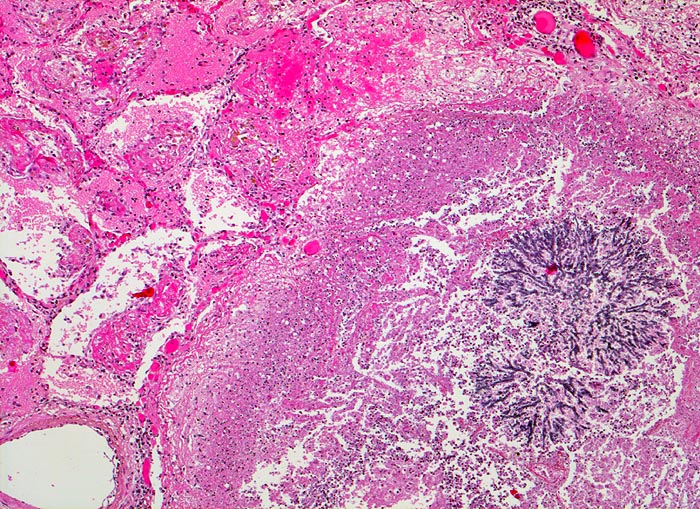

PathoPic – image database / PathoPic ID 4822 - Aspergilluspneumonie

Aspergilluspneumonie

Herd mit zentraler Einschmelzung (nekrotischer Detritus und zerfallende Granulozyten). Im Zentrum der Nekrose verzweigtes Aspergillusmycel. Die Kapillaren der angrenzenden Alveolen sind hyperämisch. In den Alveolarlichtungen sind Fibrinexsudate nachweisbar.

Seit 14 Monaten bekannte chronische lymphatische Leukämie behandelt mit Chemotherapie. Der Patient entwickelt unter Therapie eine Pneumonie und verstirbt an einer Pilzsepsis.

Es handelt sich im vorliegenden Fall um eine akute fibrinöse Entzündungsreaktion. Chronische Aspergilluspneumonien kommen ebenfalls vor.